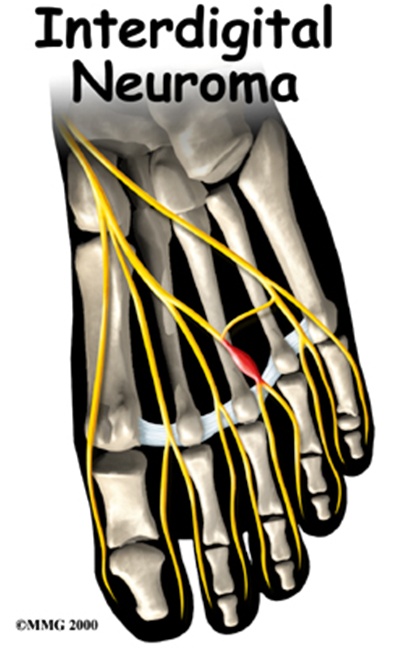

4. 지간신경종

무너진 아치로 인해 발가락 사이가 좁아지면서 신경이 압박되어 지간신경종이 발생할 수 있습니다. 스퀴즈 테스트(발가락을 쥐고 짜보는 검사)에서 극심한 통증이 나타납니다. 부산 지역에서 평발교정을 받으면 이러한 합병증을 예방할 수 있습니다.